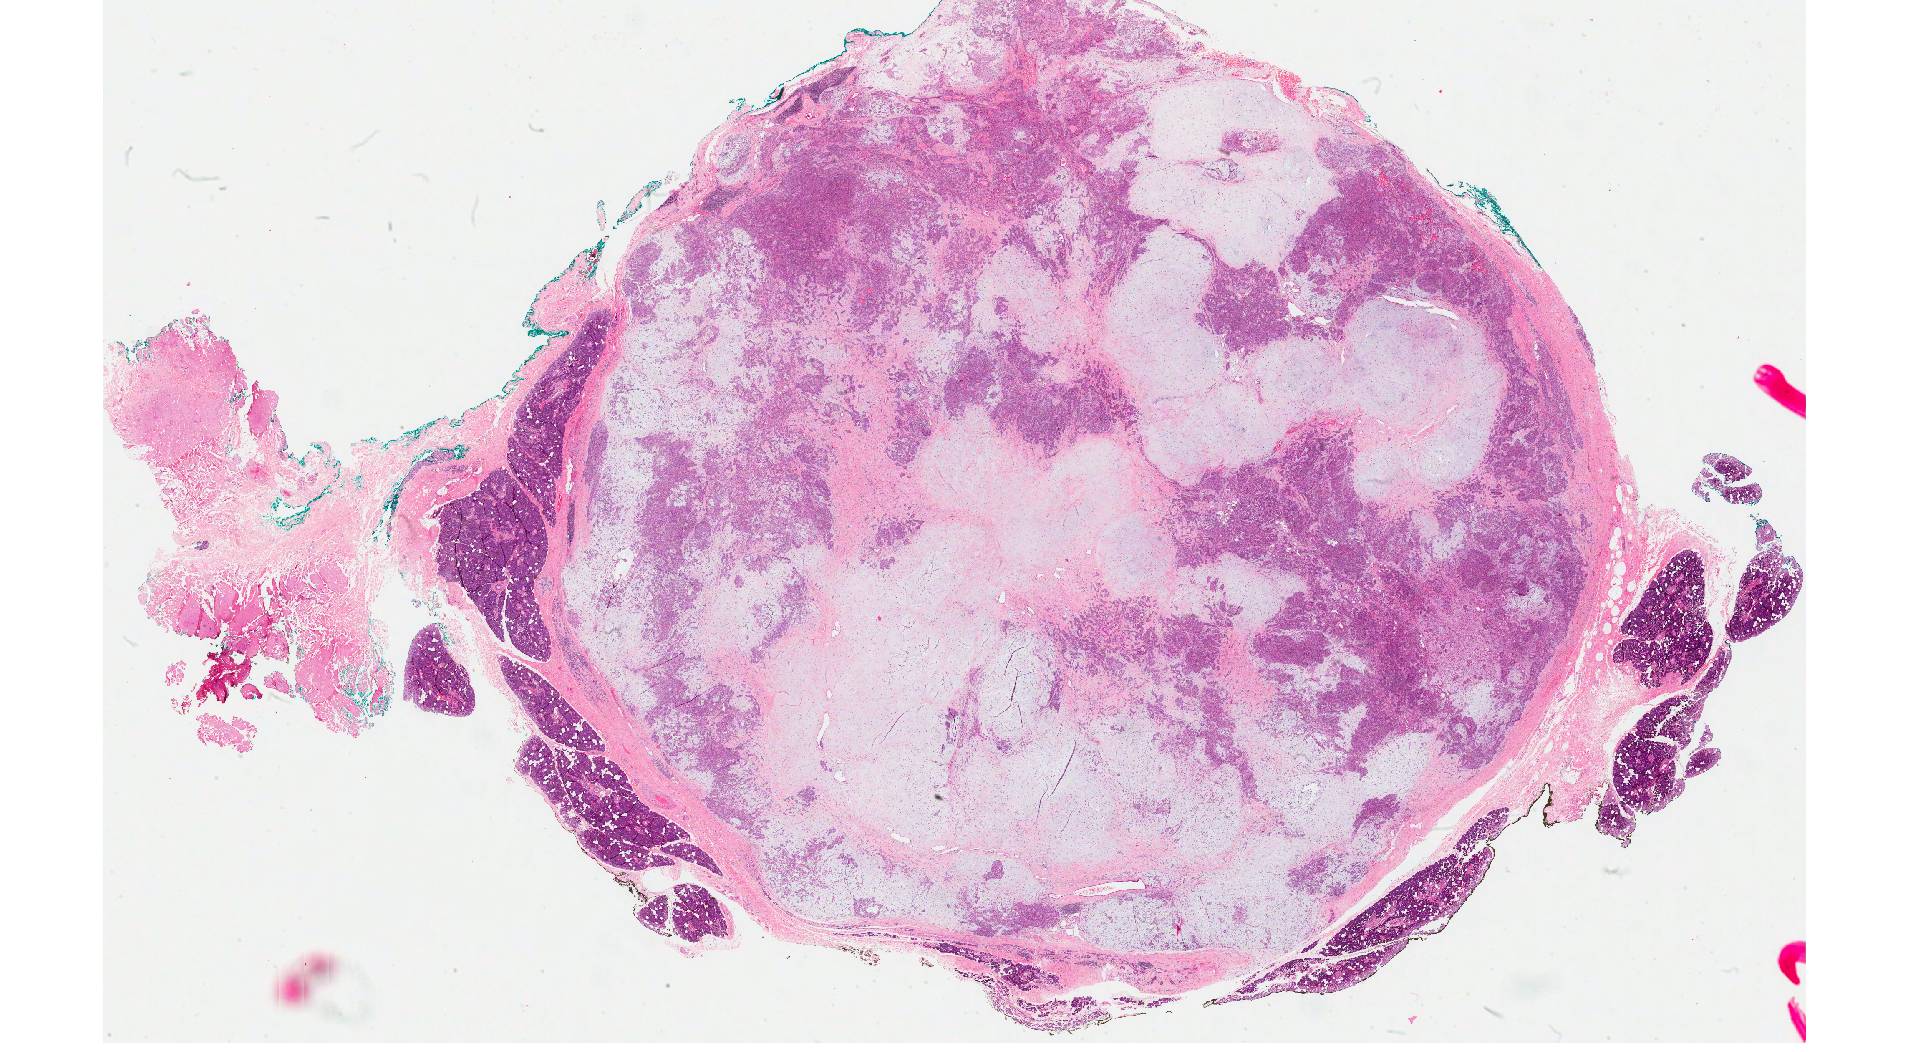

多形性腺腫由来癌 (CXPA) は、まれなタイプの唾液腺癌です。手術と放射線療法が最も一般的な治療選択肢です。

CXPAは、多形腺腫と呼ばれる非癌性腫瘍から発生します。多形性腺腫は最も一般的なタイプの唾液腺腫瘍です。これらの腫瘍のうち CXPA になるのはほんのわずかです。

CXPA は攻撃性が高い傾向があり、速やかに治療しないと離れた身体部分に広がる可能性があります。低級品種と高級品種があります。高グレードの CXPA は通常、肺やリンパ節などの離れた組織に急速に広がります。

CXPA はまれであり、ほとんど理解されていませんが、多形性腺腫と呼ばれる良性腫瘍から発生します。多形性腺腫は以下から構成されていると考えられています 45%~75%唾液腺腫瘍のこと。このうち CXPA になるのはほんのわずかです。

CXPAを他の種類の唾液腫瘍と区別するには、細針吸引が必要です。組織サンプルは研究室に送られ、医師は細胞の種類と特定の遺伝子マーカーを調べることができます。